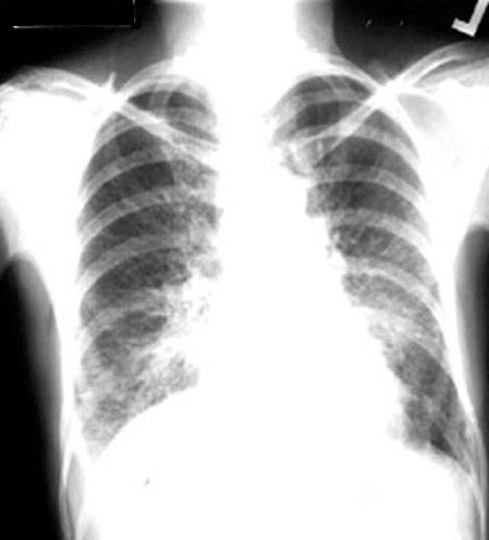

55 year old female presents with severe shortness of breath of two months duration. History of bilateral mastectomy for cancer breast 10 years back.

Findings:

• Kerley lines

• Full hilum

• Subpulmonic effusion on right

Diagnosis

Lymphangitic spread Cancer Breast